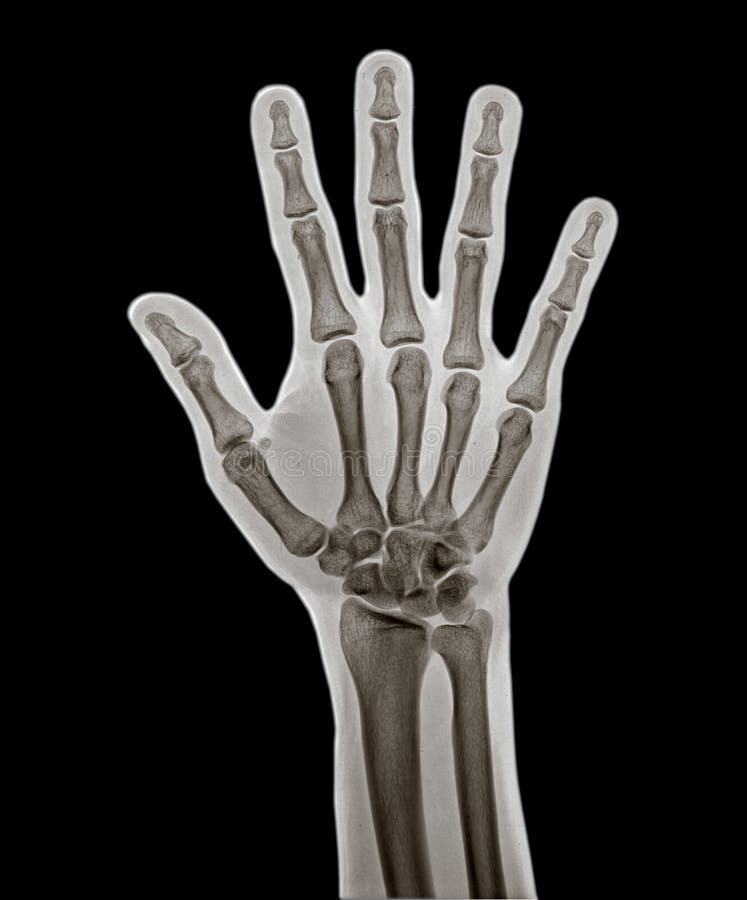

From www.dreamstime.com

Human Anatomy in Front on X Ray View. Anatomy Human Body Connection Fingers X Ray Anatomy Radiographs are usually adequate to delineate the specific osseous abnormality following trauma. The hand comprises the metacarpal and phalangeal bones. Fractures and dislocations are usually straightforward to identify, so long as the potentially injured bone is fully visible in 2 planes. Evaluation in other clinical settings such as suspected arthritis. The finger series is comprised, conventionally of a posteroanterior, oblique. Fingers X Ray Anatomy.